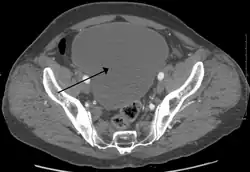

| Urinary retention with greatly enlarged bladder as seen by CT scan. | |